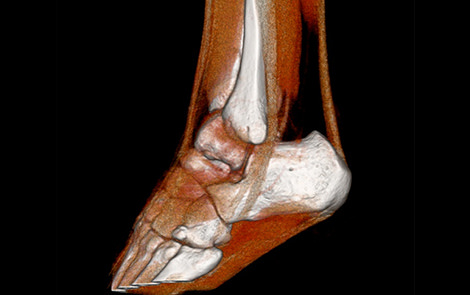

16列マルチスライスCT装置 Aquilion Lightning(キャノンメディカルシステムズ製)を導入しており骨折の診断、手術前計画目的の撮影、骨癒合経過観察目的で検査を行っています。CTでは撮影した元データより様々な断面の画像を再構成(MPR画像)でき、骨の外観のような三次元的な画像(VR画像)も作成でき、レントゲンでは評価しづらい細かい骨折の診断などにも優れています。撮影時間は数分で終わります。